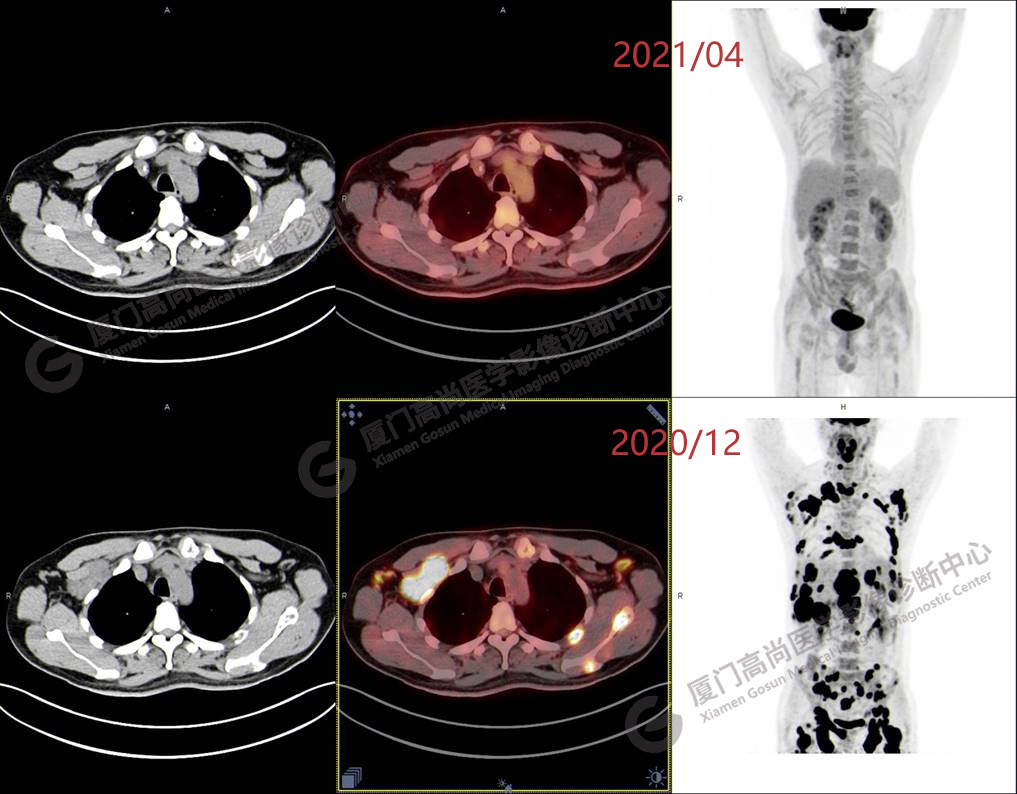

2020.12月本中心PET/CT示:全身多發(fā)腫大淋巴結(jié),代謝不同程度增高;肝臟多發(fā)稍高密度結(jié)節(jié)、脾臟多發(fā)稍低密度結(jié)節(jié),代謝異常增高;全身多發(fā)骨骼溶骨性骨質(zhì)破壞,代謝異常增高,胸2、腰1椎體病理性骨折,診斷為淋巴瘤。隨后,病理確診為彌漫大B細(xì)胞淋巴瘤。

患者化療4個(gè)療程后,于2021.04月返我中心復(fù)查,現(xiàn)患者本人已能自主行走,此次更是獨(dú)自一人來我中心復(fù)查PET/CT。檢查結(jié)果顯示:原全身多發(fā)病灶基本消失,且病灶代謝基本恢復(fù)正常。以下是患者PET/CT前后對(duì)比圖像:

PET/CT前后對(duì)比圖像1